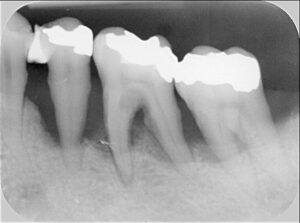

Knochenrückgang: nur durch Röntgen sicher zu erkennen

Die Sondierung zeigt, wie tief die Taschen sind. Aber sie zeigt nicht, wie viel Knochen bereits verloren gegangen ist. Dafür braucht es ein Röntgenbild.

Das OPG (Orthopantomogramm) ist eine Übersichtsaufnahme beider Kiefer. Es zeigt auf einen Blick, wo Knochen fehlt – und wie viel. Der Zahnarzt kann erkennen, ob der Abbau horizontal verläuft (gleichmäßig um den Zahn herum) oder vertikal (trichterförmig an einzelnen Stellen). Vertikale Defekte sind oft besser behandelbar.

Bei unklaren Befunden kommen zusätzlich Einzelaufnahmen (Zahnfilme) zum Einsatz. Sie zeigen einzelne Zähne detaillierter. Ein DVT (digitale Volumentomografie) kann in Ausnahmefällen hilfreich sein, etwa vor chirurgischen Eingriffen.

Ohne Röntgenbild keine vollständige Parodontitisdiagnose. Die Taschentiefe allein sagt nicht, wie viel Knochen noch vorhanden ist – und damit wie die Prognose aussieht.